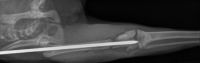

radiographie thorax chatenclouage centro médullaire fémurfracture fémur

Fracture